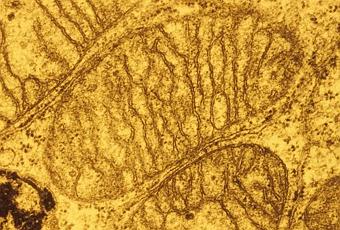

Image en microscopie électronique de trois mitochondries d’une cellule de foie en culture. Les mitochondries jouent un rôle essentiel dans les réactions qui permettent à nos cellules de produire, à partir de l’oxygène, l’énergie qui nous est indispensable, sous la forme de molécules d’ATP (adénosine triphosphate).

Source iconographique et légendaire: http://www.inserm.fr/espace-journalistes/la-levure-un-outil-dans-la-recherche-sur-les-maladies-mitochondriales